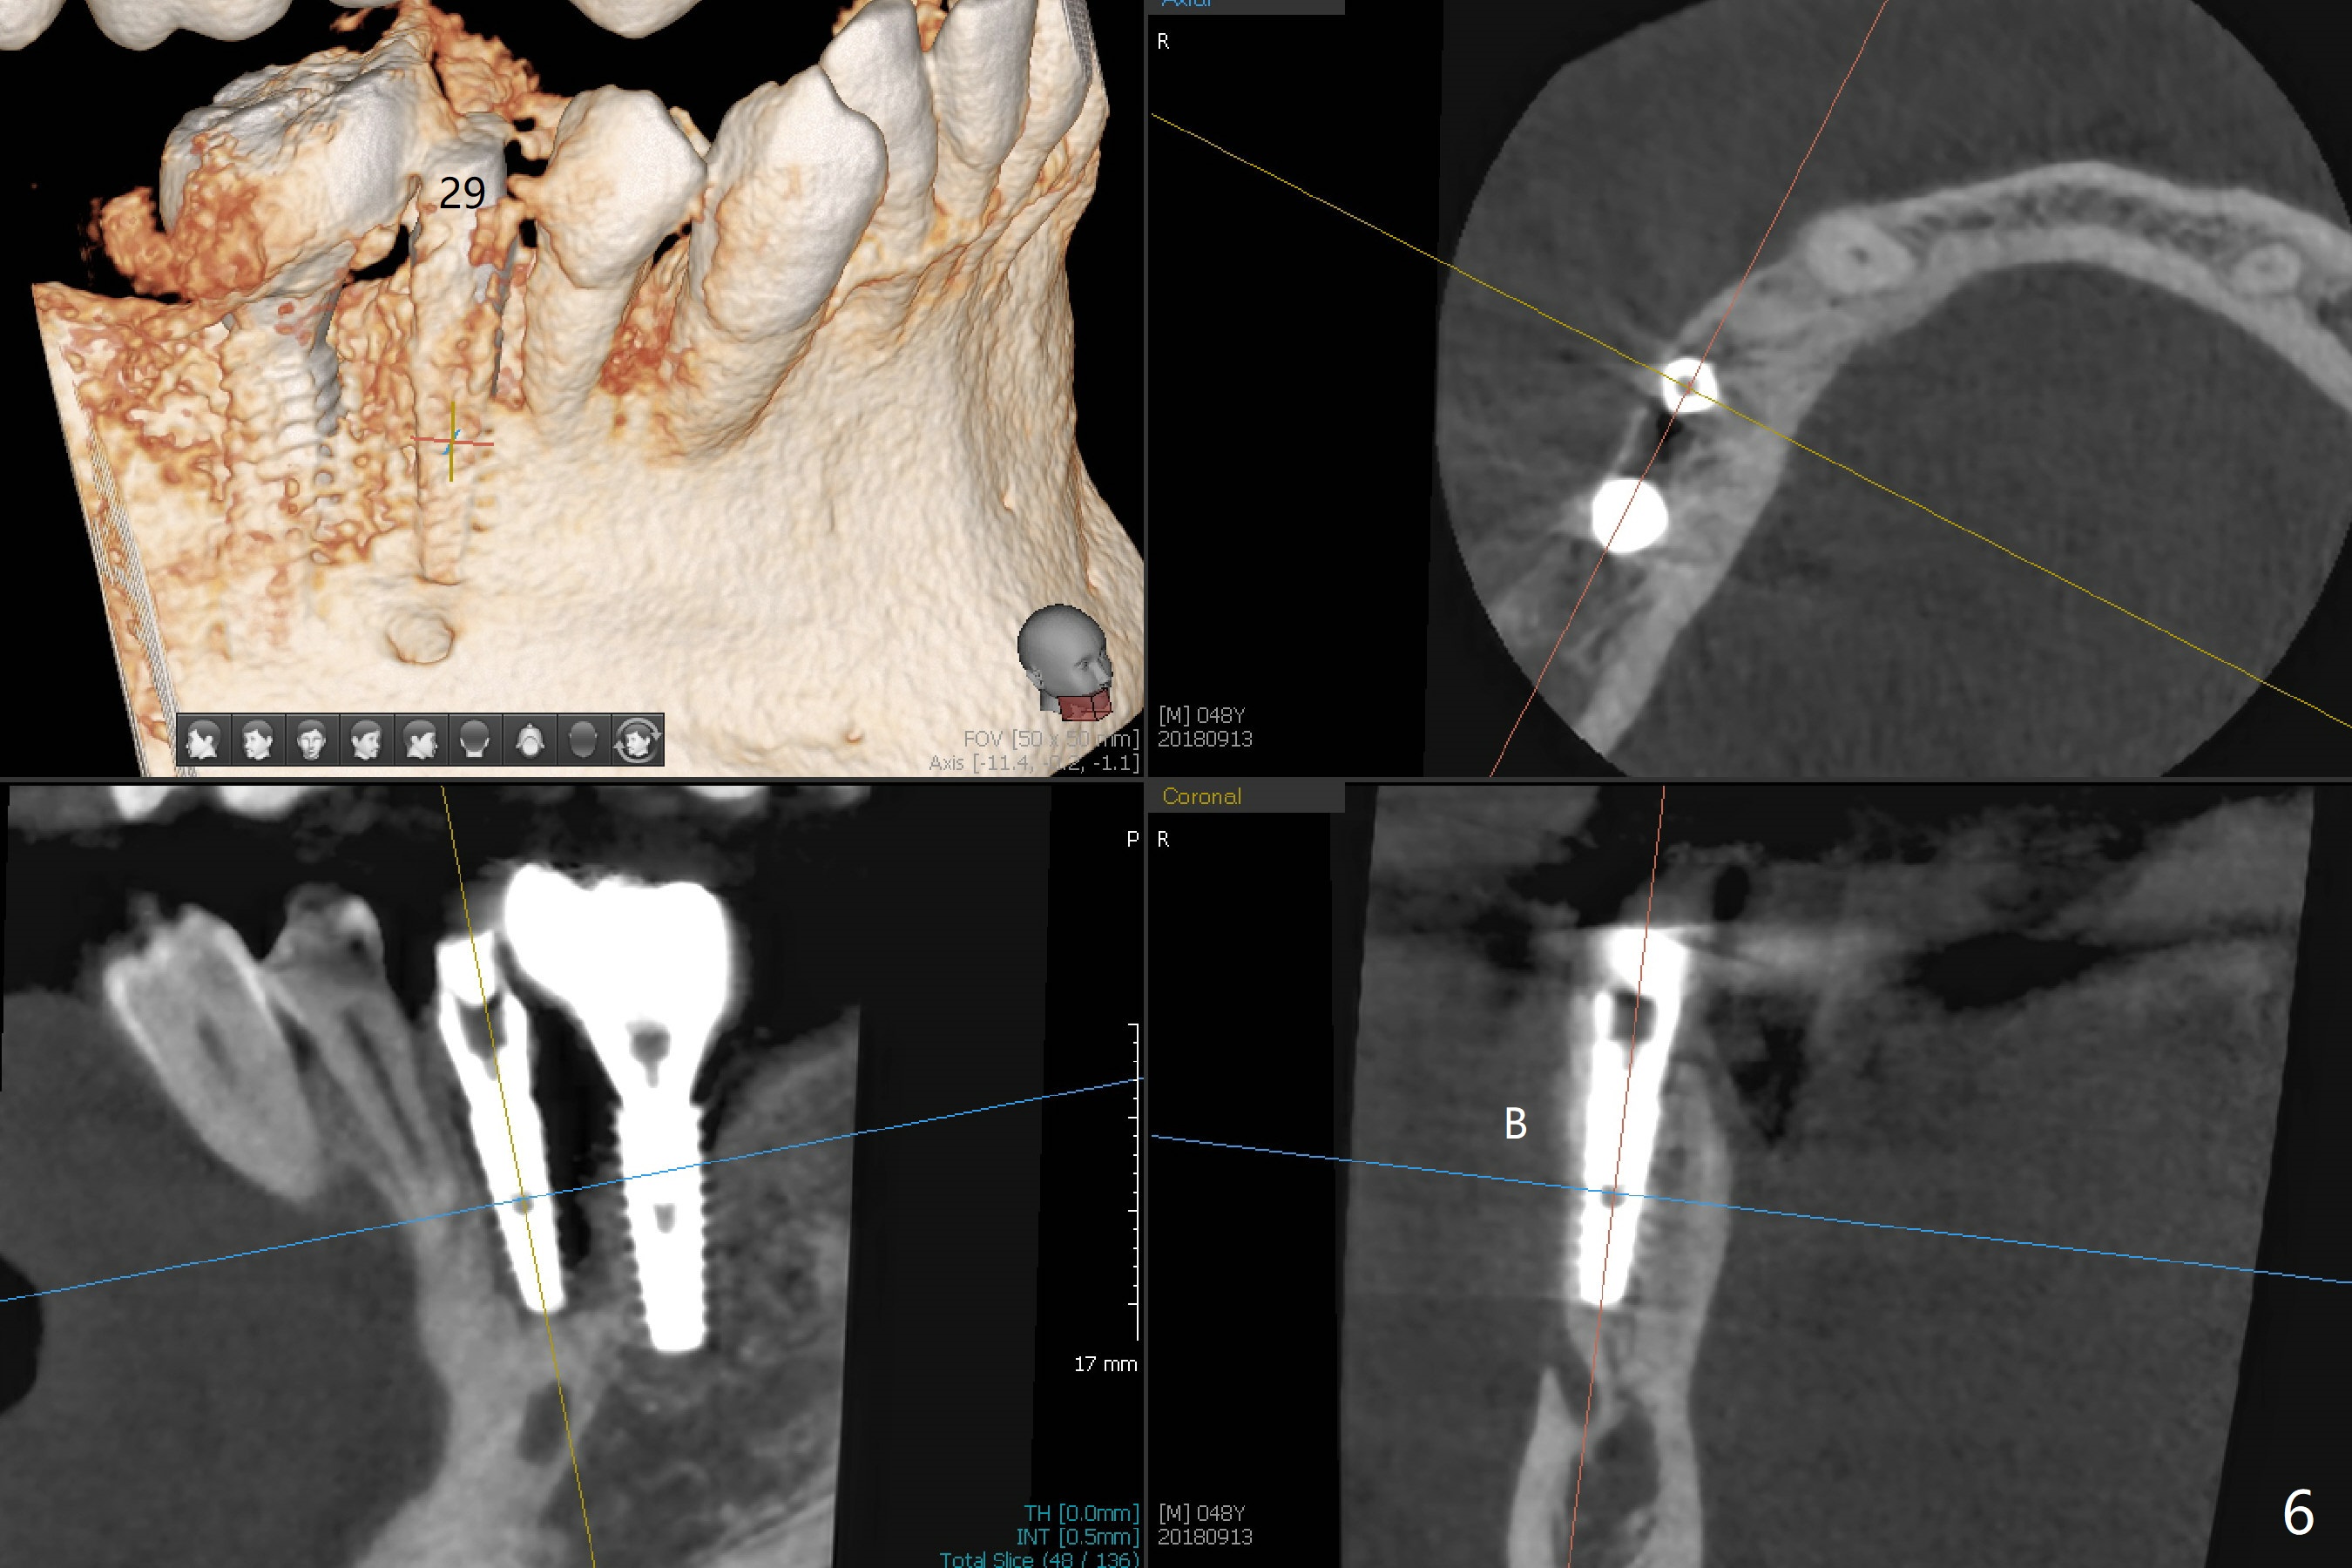

The tooth #29 has mild persistent pain radiating to the temple with mild percussion and mobility I 4.5 months post apicoectomy; the buccal recession is noticeable (Fig.1). Granulation tissue and bone graft are attached to the resected apex of the extracted tooth (Fig.2 <). The initial osteotomy with 1.5 mm drill is distal (Fig.3). After position adjustment with difficulty because of hard bone, osteotomy is finished with 2.8 and 3.2 mm Magic Drills (Fig.4). Following final drill, a 3.5x11 mm IBS implant is placed with insertion torque of 45 Ncm. With placement of a 4.5x4(4) mm abutment, Vanilla graft is placed in the buccal gap (Fig.5). Immediately postop CT shows that the implant is buccally placed (Fig.6,7 B). In fact after extraction (Fig.8), the initial osteotomy should start obliquely and as coronal and lingual as possible (Fig.9 red line). Following the initial penetration, the osteotomy should be straightened (Fig.10) so that the implant could be placed lingually (Fig11 green) to reduce buccal thread exposure. In fact there is also buccal thread exposure at #30 (Fig.12). The bone loss at #29 and 30 is minimal 4 months postop (#29, Fig.13 *)) and severe with periimplantitis at #29 one year post cementation (Fig.14). Incision will be made to exposure buccal threads of #29 and 30. If threads are within bone boundary, bone graft will be done with sticky bone after Titanium brush. If not, remove implant threads and bone graft. The worst scenario will be handled with implant removal (trephine bur 4/5 mm), either with bone graft or implant being placed lingually (IBS 3x11 mm 2-piece, to be buried, if needed (Fig.15)). Take preop photos to show #29 and 30 buccal recession and gingival erythema.